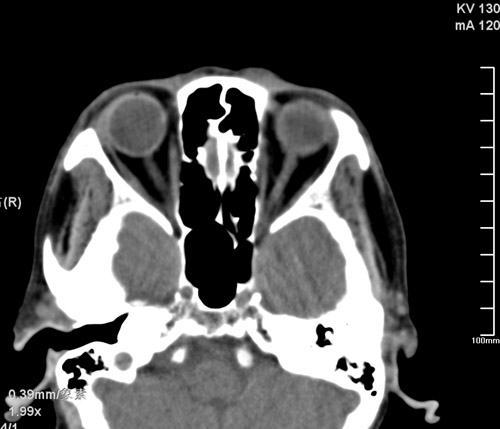

标题: CT17755:女,74 左鼻旁肿胀半年,临床以左上颌窦旁占位行CT [打印本页]

标题: CT17755:女,74 左鼻旁肿胀半年,临床以左上颌窦旁占位行CT

ct考虑鼻前庭囊肿 或鼻翼基底部慢性炎症,左上颌窦少许炎症 请指教

1)考虑左侧鼻前庭囊肿并感染。2)双侧上颌窦炎。

左侧鼻前庭囊肿并感染。双侧上颌窦炎。支持